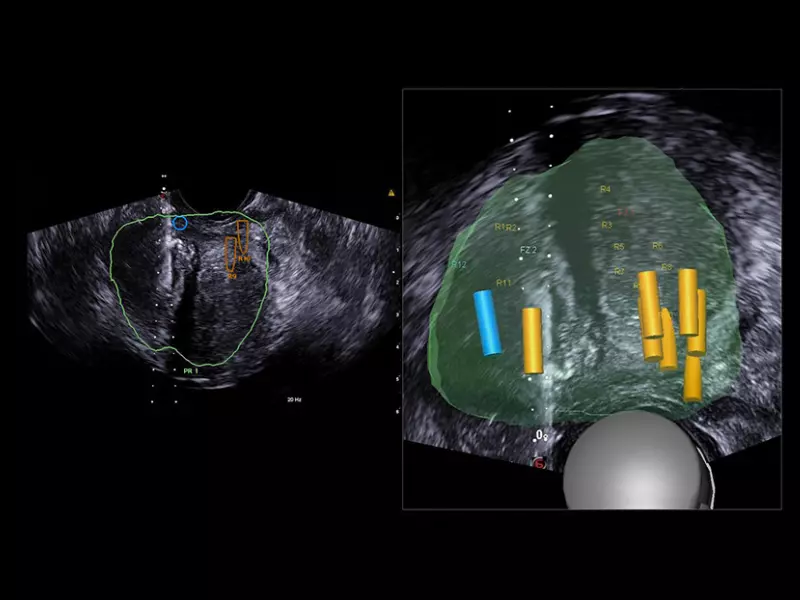

MyLab™E80 - Urofusion - TP Biopsy

MyLab™E80 - Urofusion - TP Biopsy

MyLab™E80 - Urofusion - Systematic Biopsy Guide

MyLab™E80 - Urofusion - Systematic Biopsy Guide

MyLab™E80 - Urofusion - Sample Mapping

MyLab™E80 - Urofusion - Sample Mapping